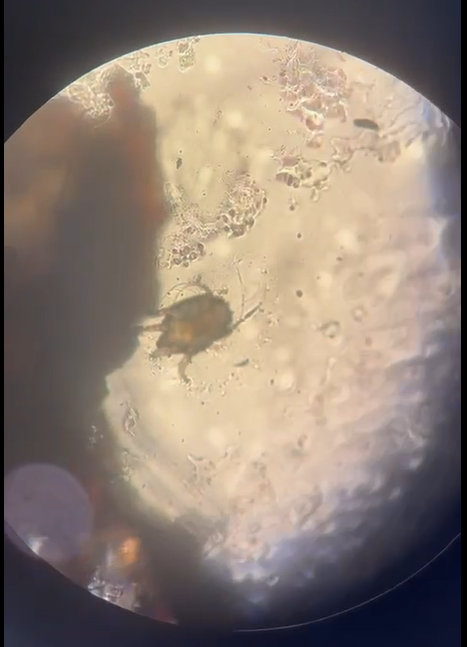

Фото предоставлено дерматологом Хаджи Е.И.

Диагностика: Содержимое ушных ходов исследуют под микроскопом.